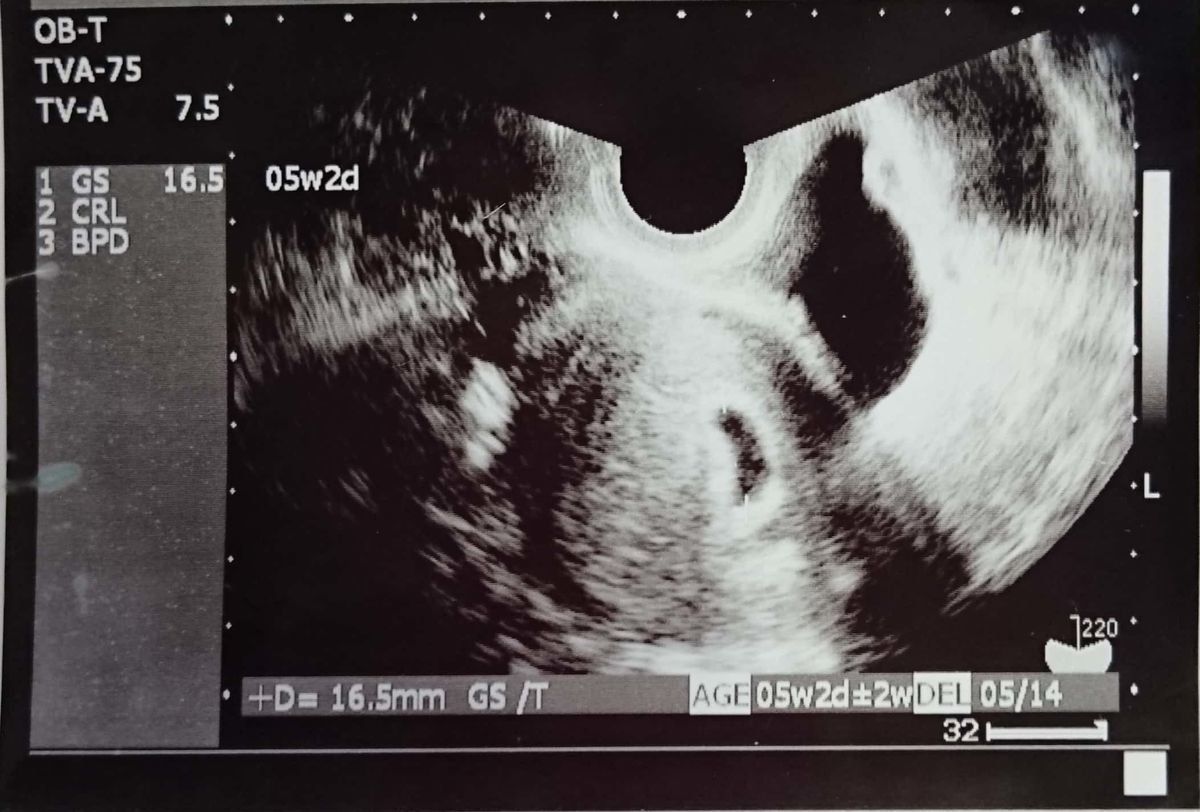

妊娠5週のエコー写真 胎嚢を確認後、不正出血で絶対安静に

D(胎嚢):16.5m

めまいを覚えたことから妊娠を疑い、その頃は計算上で妊娠3週目程度だったため、そこから2週間待って病院へ。エコー写真ではまだ胎嚢(中央の小さな縦長の黒い部分)しか確認できません。2度の流産経験から胎嚢を見るのは3回目で、「ぬか喜びをしてはいけない」と自分に言い聞かせていました。この翌日の夜、不正出血があり、自宅で絶対安静と言われました。「気休めだけど」と言われた薬を飲んで、トイレと食事以外は起きない生活が2週間続きました。